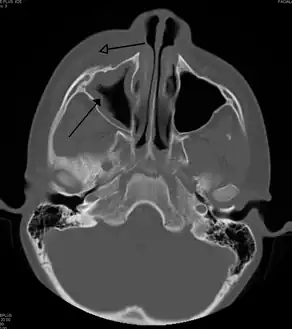

CT of chronic sinusitis

CT scan of chronic sinusitis, showing a filled right maxillary sinus with sclerotic thickened bone

Maxillary sinusitis caused by a dental infection associated with periorbital cellulitis